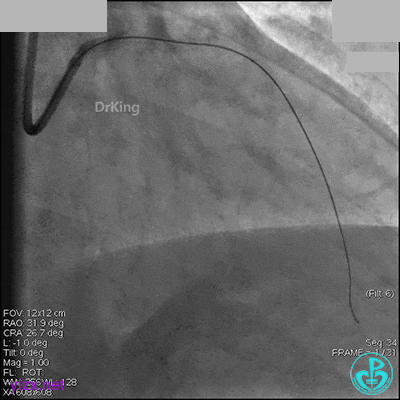

先处理前降支开口严重狭窄并顺利植入前降支到左主干支架。

没有说明是否进行了右冠脉介入治疗。